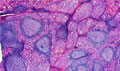

• š(4)Chronic thyroiditis (Hashimoto disease)

Macroscopic findings. The thyroid gland is diffusely enlarged with white surface when cut.